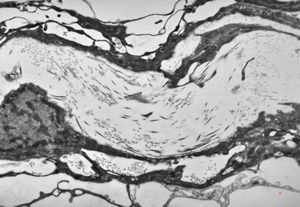

F,13y. | n.suralis … axonal neuropathy … Charcot-Marie-Tooth disease

Demyelinized nerve with bands of Büngner (square, inset) . P- perineurium, | E - epineurium. (Human, sural nerve.) Scale 0.2 mm.